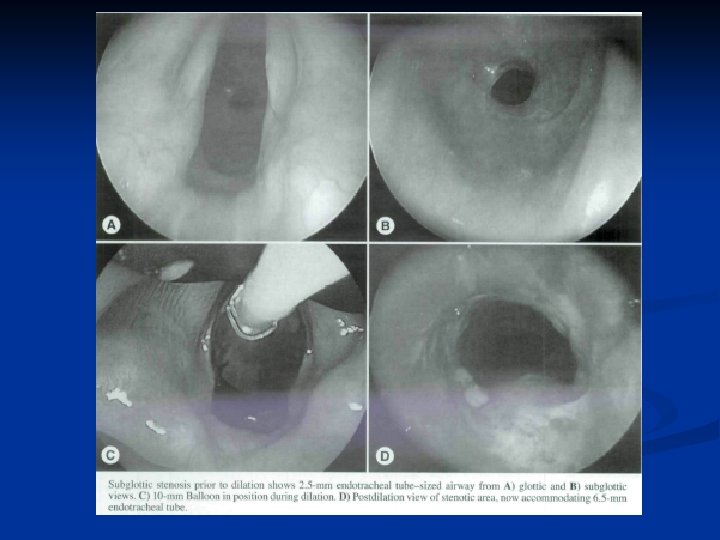

SGS Balloon Dilation of bronchtracheal stenoses with angioplasty balloons described previously in adults and children +/- stents n Advantage compared to rigid or bougie dilation n Balloons maximize the radial direction and pressure of dilation n Less damaging to tracheal wall mucosa n Found to have good initial results n n Often requires stenting of dilated portion n Repeated procedures necessary in active processes, e. g. Autoimmune States

SGS Balloon Dilation n n Lee and Rutter (2008) 6 patients with IPSS (single discrete stenosis) Underwent dilation with 10 to 14 mm balloon in either single or 2 consecutive dilation (in 7 days) F/u between 10 and 30 months in 4 patients n n n No symptoms of recurrent airway stenosis One patient required repeat dilation after 22 mos No adverse effects or complications Recommended burst pressure (8 to 17 atm) 4 cm long catheters, center of balloon positioned at midpoint of stenosis Airway dilated from 2. 0 to 3. 5 ET size larger than initial size

Endoscopic Balloon Dilation